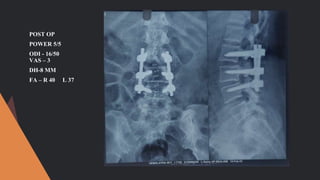

POWER - 5/5

ODI - 24

VAS - 5

DH - 6MM

FA - R 76 L 66

NO LLS